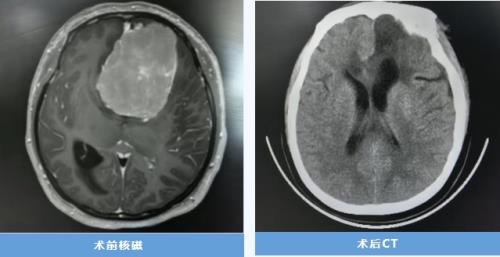

生死竞速!交大一附院榆林医院成功救治颅内大量出血患者

生命接力!多学科协作为高危孕妇摘除巨大脑膜瘤,母子平安